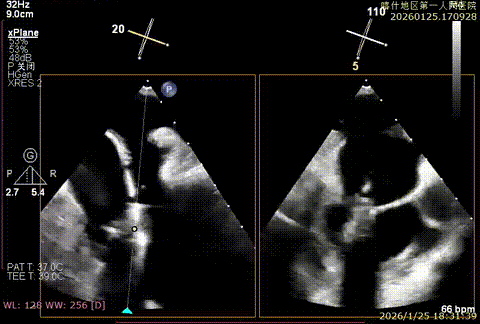

重度反流

3D enface进行Orientation调整

捕捞并夹持瓣叶

反流降低

第二枚XTR定位

Orientation调整

捕捞并夹持瓣叶,反流有效降低

组织桥稳定

术后平均跨瓣压差3mmHg

该例患者为DMR,脱垂区域较宽,术前制定手术策略:使用2把XTR先于患者外侧交界至1区部位进行钳夹。术中房间隔穿刺高度为4.0cm。成功穿刺后将SGC和XTR-CDS依次送入左心房,通过操控“M”旋钮调节SGC,使二尖瓣夹避开华法林脊,成功定位于2区正上方。在2区进行弹道测试成功后,进行Orientation调整。第一把于外侧交界区夹持,第二把于1区夹持,术中成功捕捞和夹持瓣叶后缓慢关紧夹臂,TEE检查见二尖瓣反流程度降低至1+,术后平均跨瓣压差3mmHg,手术顺利结束。